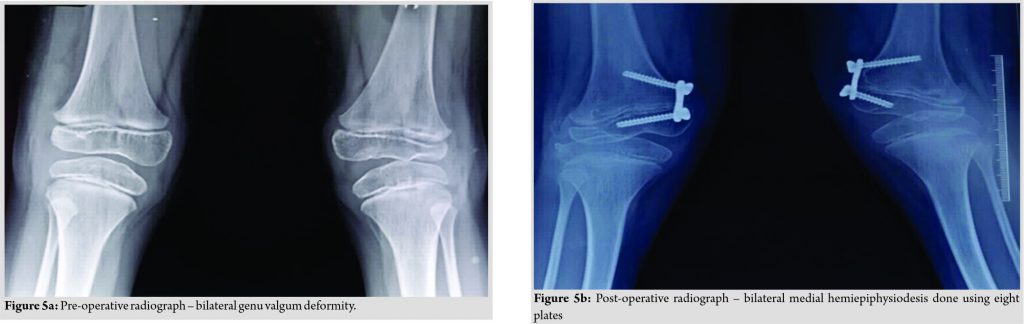

The patient had unassisted bipedal gait with bilateral intoeing and equinus at the right ankle. There was bilateral genu valgum deformity with patellar subluxation. The clinical tibiofemoral angle was 13° on the right side and 15° on the left side. The Apprehension test for a patellar subluxation was negative. There was an extension lag of 10° on both knees and equinus deformity of 20° at the right ankle. Bilateral metatarsus adductus was present. Radiographs of the pelvis with both hips revealed bilateral rudimentary femoral epiphysis with fragmentation (Fig. 3).

erial casts for foot deformity were applied but there was no improvement. Metatarsus adductus on each side was corrected by multiple dome osteotomies of metatarsals (Fig. 4a, b). Surgical correction of bilateral genu valgum by medial distal femoral hemiepiphysiodesis was done (Fig. 5a, b). The right side equinus deformity was treated by the Vulpius V-Y plasty of gastrosoleus aponeurosis. On the latest follow-up at 1 ½ years post-surgery, residual genu valgum deformity was noted on the left side and so osteotomy at appropriate age was planned. Clinical correction of metatarsus adductus was achieved with a plantigrade foot (Fig. 6).